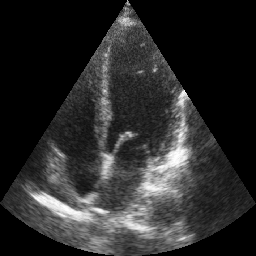

Transthoracic echo is one of the most common means of cardiac studies in the clinical routines. During the echo exam, the sonographer captures a set of standard cross sections (echo views) of the heart. Each 2D echo view cuts through the 3D cardiac geometry via a unique plane. Consequently, different views share some limited information. In this work, we investigate the feasibility of generating a 2D echo view using another view based on adversarial generative models. The objective optimized to train the view-conversion model is based on the ideas introduced by LSGAN, PatchGAN and Conditional GAN (cGAN). The size and length of the left ventricle in the generated target echo view is compared against that of the target ground-truth to assess the validity of the echo view conversion. Results show that there is a correlation of 0.50 between the LV areas and 0.49 between the LV lengths of the generated target frames and the real target frames.